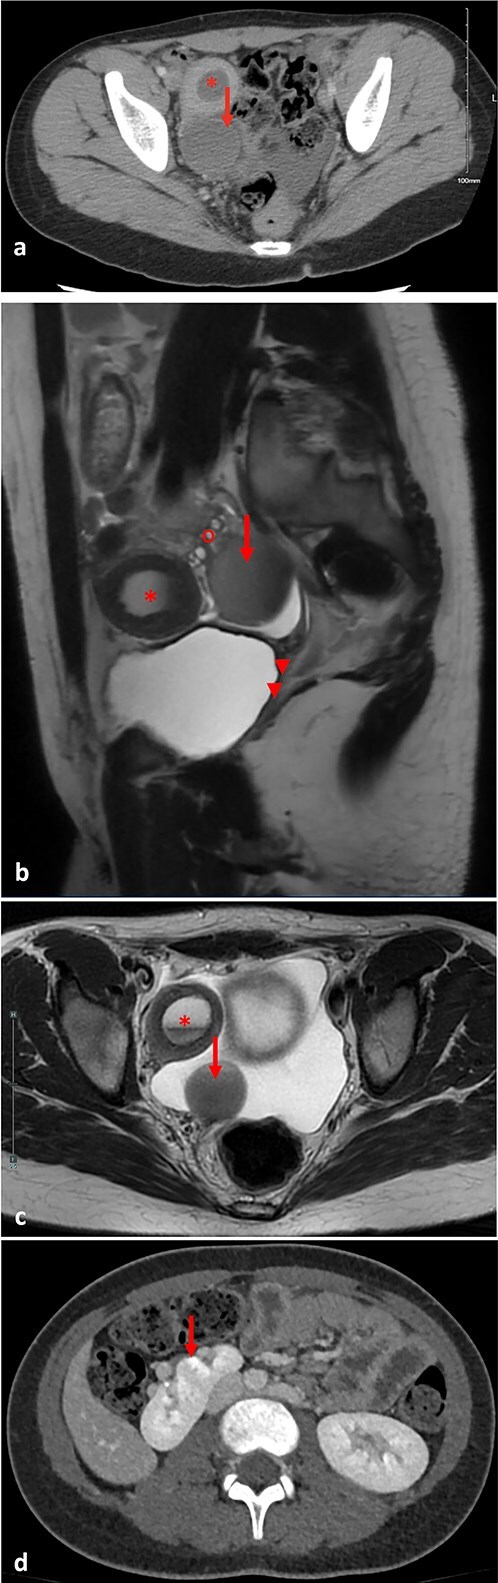

MRKH综合征(mayer - rokitansky - k - hauser综合征)是一种生殖道畸形,发生率约为5000分之一。其特点是先天性发育不全或明显的苗勒管衍生结构发育不全。大约3%的MRKH患者有正常的子宫。一名12岁健康女性,表现为持续周期性严重右下腹疼痛。她被发现有MRKH综合征,右侧子宫功能正常,有子宫积血和同侧输卵管积血。随后,她接受了诊断性膀胱镜检查、阴道镜检查和盆腔腹腔镜检查。腹腔镜下行子宫积血、输卵管积血引流,子宫造口置管及子宫前腹壁固定。术后症状完全消失。2周后的计算机断层扫描显示血肿消退,输卵管积血明显改善。子宫功能正常的MRKH综合征可能表现为青春期女性患者的周期性腹痛。腹腔镜子宫引流放置是一种治疗选择。

Mayer-Rokitansky-Küster-Hauser (MRKH) syndrome is a reproductive tract malformation occurring in ~1 in 5000 female births. It is characterized by congenital agenesis or marked hypoplasia of the Mullerian ducts derivative structures. About 3% of MRKH patients have a functioning uterus. A 12-year-old otherwise healthy female presented with persistent cyclic severe right lower quadrant pain. She was found to have MRKH syndrome with a right-sided functioning uterus and hematometra and ipsilateral hematosalpinx. She subsequently underwent diagnostic cystoscopy, vaginoscopy, and pelvic laparoscopy. Laparoscopic drainage of the hematometra and hematosalpinx, and hysterostomy catheter placement and uterine fixation to anterior abdominal wall were performed. Symptoms fully resolved post-operatively. A computed tomography scan 2 weeks later demonstrated resolution of the hematometra and significant improvement in the hematosalpinx. MRKH syndrome with a functioning uterus may present as cyclic abdominal pain in adolescent female patients. Laparoscopic uterine drain placement is a management option.